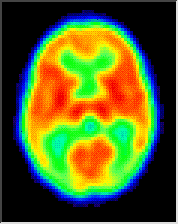

1 year

The differences between the brain from 1 month age till 1 year.